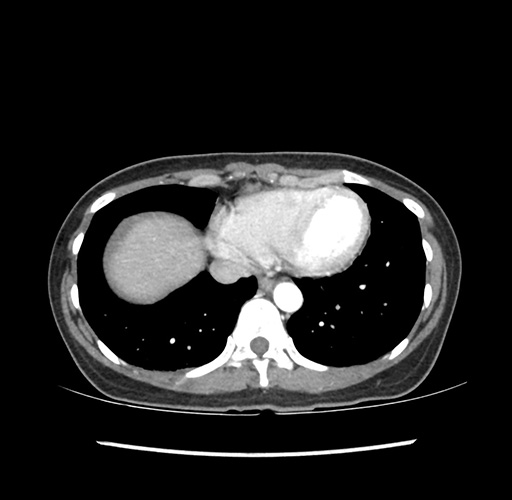

Imaging Analysis

Look through the patient's CT scan to identify any areas of concern for the necessary procedure.

Based on your CT findings, which issue(s) would give reason for "planned slowing down moment(s)" in this case?